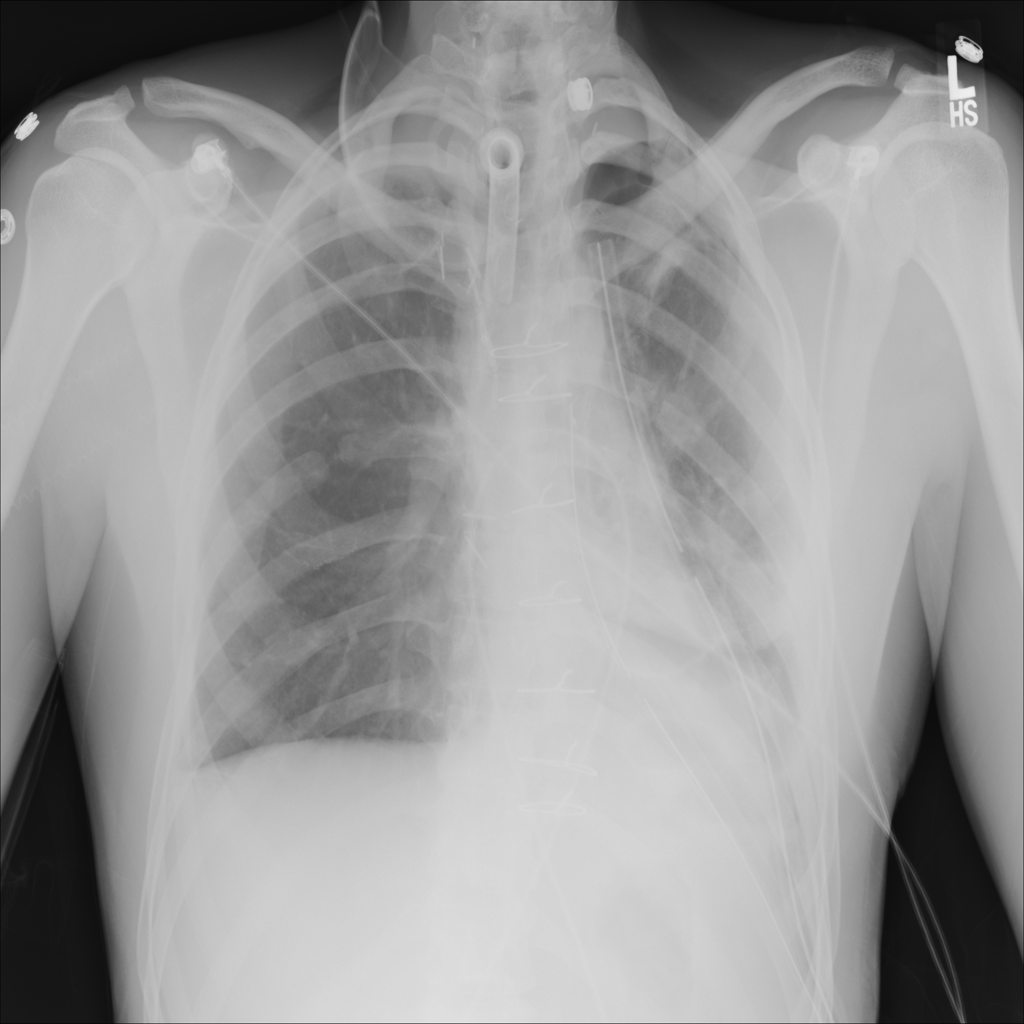

PAT-4639 · IMG-011Pneumothorax

PAT-4639 · IMG-011

AP